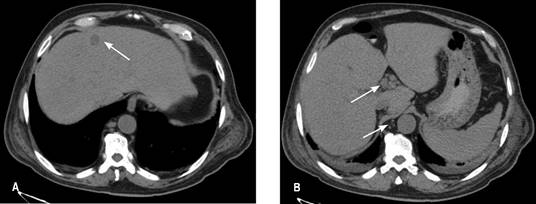

Clínicamente con estabilidad hemodinámica, abdomen distendido, doloroso a la palpación en hipocondrio derecho y fosa ilíaca derecha, se realizaron estudios de laboratorio que reportaron leucocitos 2.8 x 103 μl, neutrófilos totales 87.8%, hemoglobina 6.7 g/dl, hematocrito 20.2%, plaquetas 67 x 103 μl, bilirrubina total 3.04 mg/dl, bilirrubina directa 2.16 mg/dl, bilirrubina indirecta 0.88 mg/dl, panel viral negativo. Se practicó ultrasonografía (USG) de hígado y vías biliares que reportó colecistitis crónica litiásica con datos ecográficos de agudización y hepatomegalia de origen a determinar. La tomografía axial computarizada de abdomen reportó actividad ganglionar a nivel de hilio hepático, peripancreáticos, frénicos, paracólicos y yuxtaintestinales, así como precavos, retrocavos, interaórtico-cavales y paraaórticos, de primario a determinar. Glándula hepática con imágenes de posibles implantes metastásicos localizados en segmentos IV y VI. Vesícula biliar con pared de 6.3 mm, con contenido hipodenso, cambios por colecistitis y escaso líquido perihepático (Figura 2).

Figura 2: TC de abdomen. (A) Imagen de implante metastásico. (B) Ganglios a nivel de hilio hepático y paraaórticos.